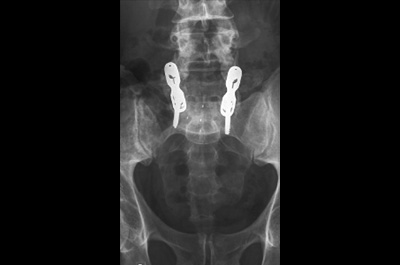

고령 및 심혈관계질환으로 전신마취와 수술 위험도가 높은 환자의 시술 사례

고령 및 심혈관계질환으로 전신마취와 수술 위험도가 높은 환자의 시술 사례 고령 및 심혈관계질환으로 전신마취와 수술 위험도가 높은 환자의 시술 사례